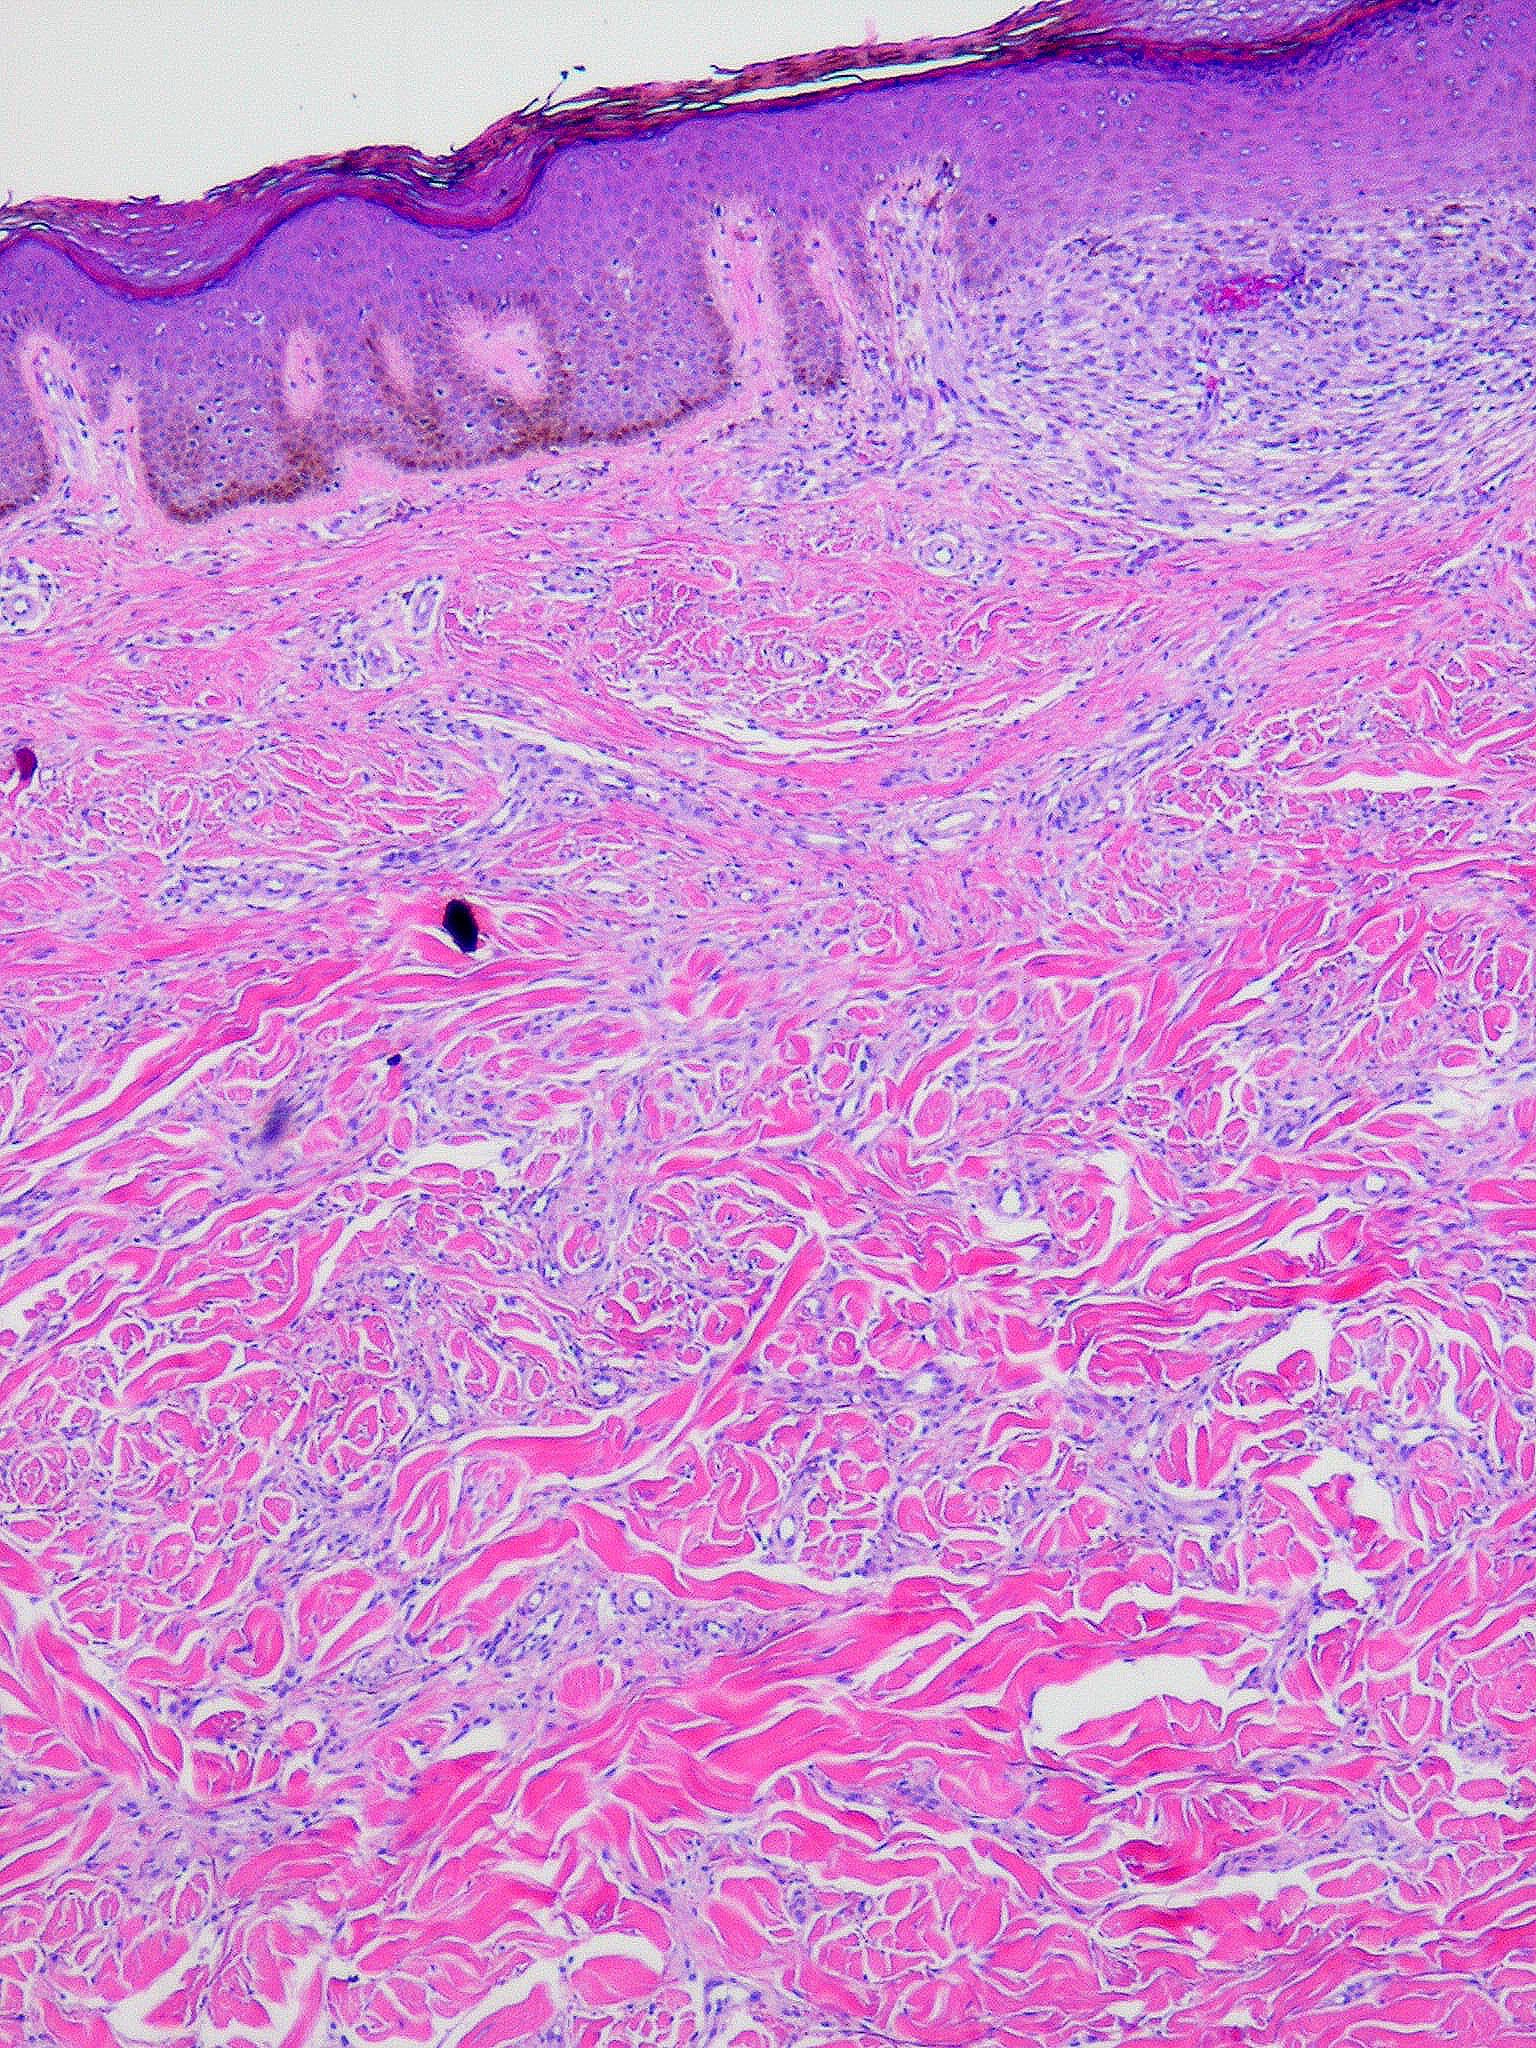

The histologic picture found in the papules in scleromyxedema resembles that observed in lichen myxedematosus. In the diffusely thickened skin, there is extensive proliferation of fibroblasts throughout the dermis associated with irregularly arranged bundles of collagen. In many areas, the collagen bundles are split into individual fibers by mucin. As a rule, the amount of mucin is greater in the upper half than in the lower half of the dermis.